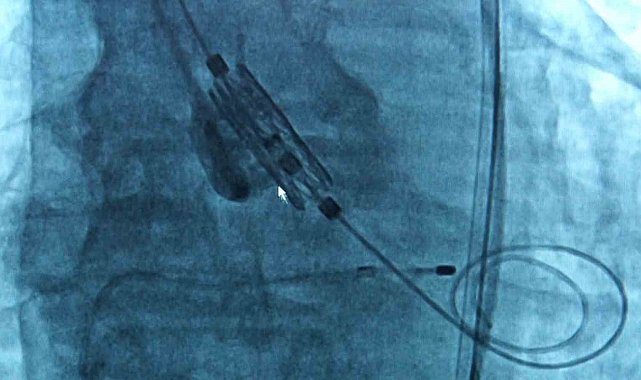

TAVI yöntemine ilişkin bilgi veren Doç. Dr. Dilay Karabulut, "Aort kapak, kalpten çıkan ana damar dediğimiz aortun ağzındaki kapak. Yaşla beraber kapakta gelişen kireçlenme ve kalsifikasyon((Vücut dokusunda kalsiyum birikmesi)a bağlı olarak kapaklar birbirine yapışmakta ve kapak alanı daralmaktadır. Bunun sonucunda kalp yeteri kadar kanı vücuda pompalayamadığı için hastada birtakım semptomlar gelişmekte, bu ilerleyerek kalp yetmezliğine kadar gitmekte. Kapak daraldığı zaman 2 tane tedavi yöntemimiz var; kapağın cerrahi olarak çıkarılması ya da TAVI dediğimiz yani kasıktan küçük bir kesi yapılarak kapağı yerleştirdiğimiz bir işlem. Eskiden daha çok cerrahi işlemler ön plandaydı. Ne yapıyorduk; hastanın göğüs kafesi açılıyor, kalbi durduruluyor, kapak yerinden çıkarılıyor ve yapay bir kapak takılıyordu. Şu an hala bazı seçilmiş hastalarda cerrahi aort kapak replasmanı yapılıyor ancak TAVI işlemi 20 yıldır tüm dünyada, ülkemizde de aynı şekilde yapılan bir işlem. Hasta için daha konforlu özellikle seçilmiş hasta gruplarında hastaneye yatış süresi daha kısa, hastanın göğüs kafesi açılmadan, kalbi durdurulmadan ve hastanede işlem sonrası yaklaşık 1 gün kadar kalıp hastayı taburcu ediyoruz. Nasıl yapıyoruz; kasıktan küçük bir kesi açıyoruz, bu kesiden bir telle kalbin içine doğru ilerliyoruz. Aort kapağın olduğu yere yeni yapay kapağı yerleştiriyoruz. Operasyon yaklaşık 1 saat kadar sürüyor. Yapılan çalışmalarla gösterildi ki artık orta risk hatta son zamanlarda düşük riskli olan grupta da TAVI işlemini yapabiliyoruz. Yapay kapaklar olduğu için tabi ki ilerleyen dönemlerde dejenerasyona uğrayabiliyor ama 10-15 yıllık takiplerde şu ana kadar çok olumsuz bir gelişme gösterilememiş" dedi.

TAVI yönteminde Bakırköy Dr. Sadi Konuk Eğitim ve Araştırma Hastanesi olarak yeni nesil kapaklarla işlemler gerçekleştirdiklerini ifade eden Uzm. Dr. Ersan Oflar, kullanılan formların etkisine yönelik ise şunları söyledi: "Kendinden genişleyebilen bir de balonla genişleyebilen kapak platformları var. Hastalarda balonla genişleyebilen platformlarını kullanıyorduk, şu anki balonla genişleyebilen kapak, yeni nesil bir kapak, hekim açısından kapağı hizalama açısından daha konforlu. Hekim daha iyi hizalayabiliyor, işlem süresinin kısalması avantajı var. Daha sonra hastaya koroner bir işlem gerekirse o açıdan da bize avantaj sağlıyor. Hasta açısından diğer bir konforu da TAVI işleminden sonra sık karşılaştığımız olaylardan biri de kalıcı pil ihtiyacı olabiliyor. Bu kapağın eteği biraz daha yumuşak olduğu için pil ihtiyacını da biraz daha azaltmış oluyoruz. Majör avantajı aslında hizalamayla ilgili, konumlandığınız yer çok önemli çünkü siz kapağı iyi yerleştirmezseniz ileriki dönemde kapağın ömrü daha kısa olabiliyor. Fizyolojik pozisyonu hizalayamazsanız kapak erken dönemde dejenerasyon dediğimiz bozulmalara uğrayabiliyor, bu kapakta o avantaj da var"